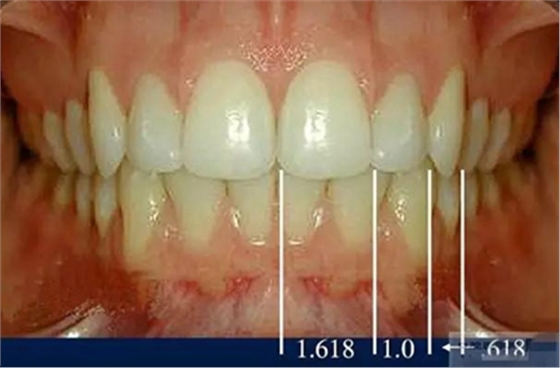

前牙的黃金分割比例

正面觀

側(cè)切牙約為中切牙的60%

尖牙約為側(cè)切牙的60%

4.牙齒比例

中切牙正常/理想的 寬/長(zhǎng)百分比約為75%—80%